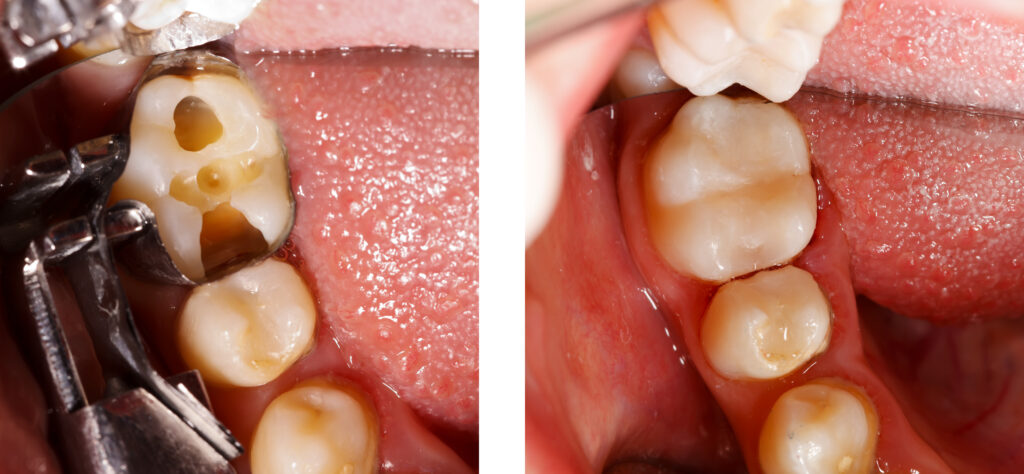

Composite Fillings

Natural-Looking Tooth Repair That Blends Seamlessly With Your Smile

Cavities and minor tooth damage don’t have to affect your confidence. At Plaza Dental Care, we offer high-quality composite (tooth-colored) fillings that restore strength, function, and appearance — all in one treatment.

Composite fillings are designed to match the natural shade of your teeth, making them virtually invisible.

What are Composite Fillings?

Composite fillings are made from a durable tooth-colored resin material that bonds directly to your natural tooth structure. Unlike traditional metal (amalgam) fillings, composite restorations blend in seamlessly with your smile.